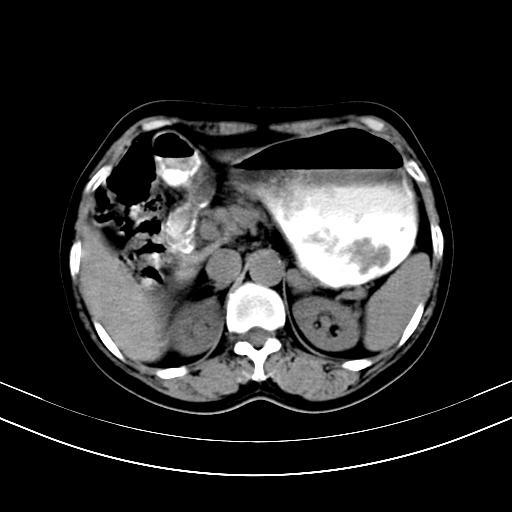

标题: CT12767:肝脏病变请会诊

补充强化片

胃内见充盈缺损,建议行胃镜病理检查,如果胃内无占位,则肝内考虑左叶、尾叶为包膜型肝癌,如有则考虑为转移瘤

胃内的充盈缺损,当时让患者俯卧位在扫描一下就 好了,当然最好是增强扫描,肝脏的病灶平扫很难定性,可以考虑是肝癌·血管瘤·转移瘤!

胃内见充盈缺损,建议行胃镜病理检查,如果胃内无占位,则肝内考虑左叶、尾叶为包膜型肝癌,如有则考虑为转移瘤,左侧肾上腺 明显增大,成结节改变,本人考虑转移瘤可能性大。

胃内的充盈缺损因胃壁不厚,我个人考虑为胃内残留物。肝左叶及尾叶病灶,我首先考虑血管瘤,其次为肝癌。(尾叶的更低密度区太规整)

肝脏左叶和尾叶均见略低密度影,尾叶病变内见坏死?其边界清晰,形态规整1血管瘤,2肝癌待排

胆囊内见一略高密度影,息肉?

1.肝左叶及尾叶占位建议增强2.肝硬化

肝脏左叶和尾叶均见略低密度影,尾叶病变内见坏死?其边界清晰,形态规整1血管瘤,2肝癌待排3建议增强。

胃内充盈缺损考虑为胃内存留物,肝左叶和尾状叶两个病灶,均为低密度,建议增强。

考虑:胃体小弯侧胃癌(或平滑肌瘤恶化或平滑肌肉瘤)伴肝转移,左侧肾上腺转移不除外.

胃内充盈缺损考虑为肿瘤,肝尾叶及左叶肿块考虑转移瘤

胃癌肝内转移及肾上腺转移。

胃窦部占位伴肝及左肾上腺转移可能大,建议增强扫描。

肝脏左叶和尾叶均见略低密度影,尾叶病变内见坏死?其边界清晰,形态规整1血管瘤,2肝癌待排3建议增强或结合临床及超声与实验室检查

肝左叶及尾叶低密度灶,增强有渐进性明显强化,考虑血管瘤。胃内“充缺”首先要排除异物(食物),变换体位可鉴别。增强时机抓的不好,还应该有延时像。

谢谢楼主的增强片子,平扫没发现左侧肾上腺的问题很不好意思,可惜片子只有门脉期,所以还只有猜,肝脏的病灶在门脉期部分强化,首先考虑为血管瘤(其他的用一种病不好解释)胃要喝水就好了现在不好说是否有问题,左肾上腺的问题考虑是肿瘤。

做了增强后,可以明确胃是没有肿瘤的,肾上腺也没有肿瘤.肝左叶的病灶首先考虑血管瘤,应该再延迟,肝尾状叶的病灶仍不能排除肝癌的可能性.